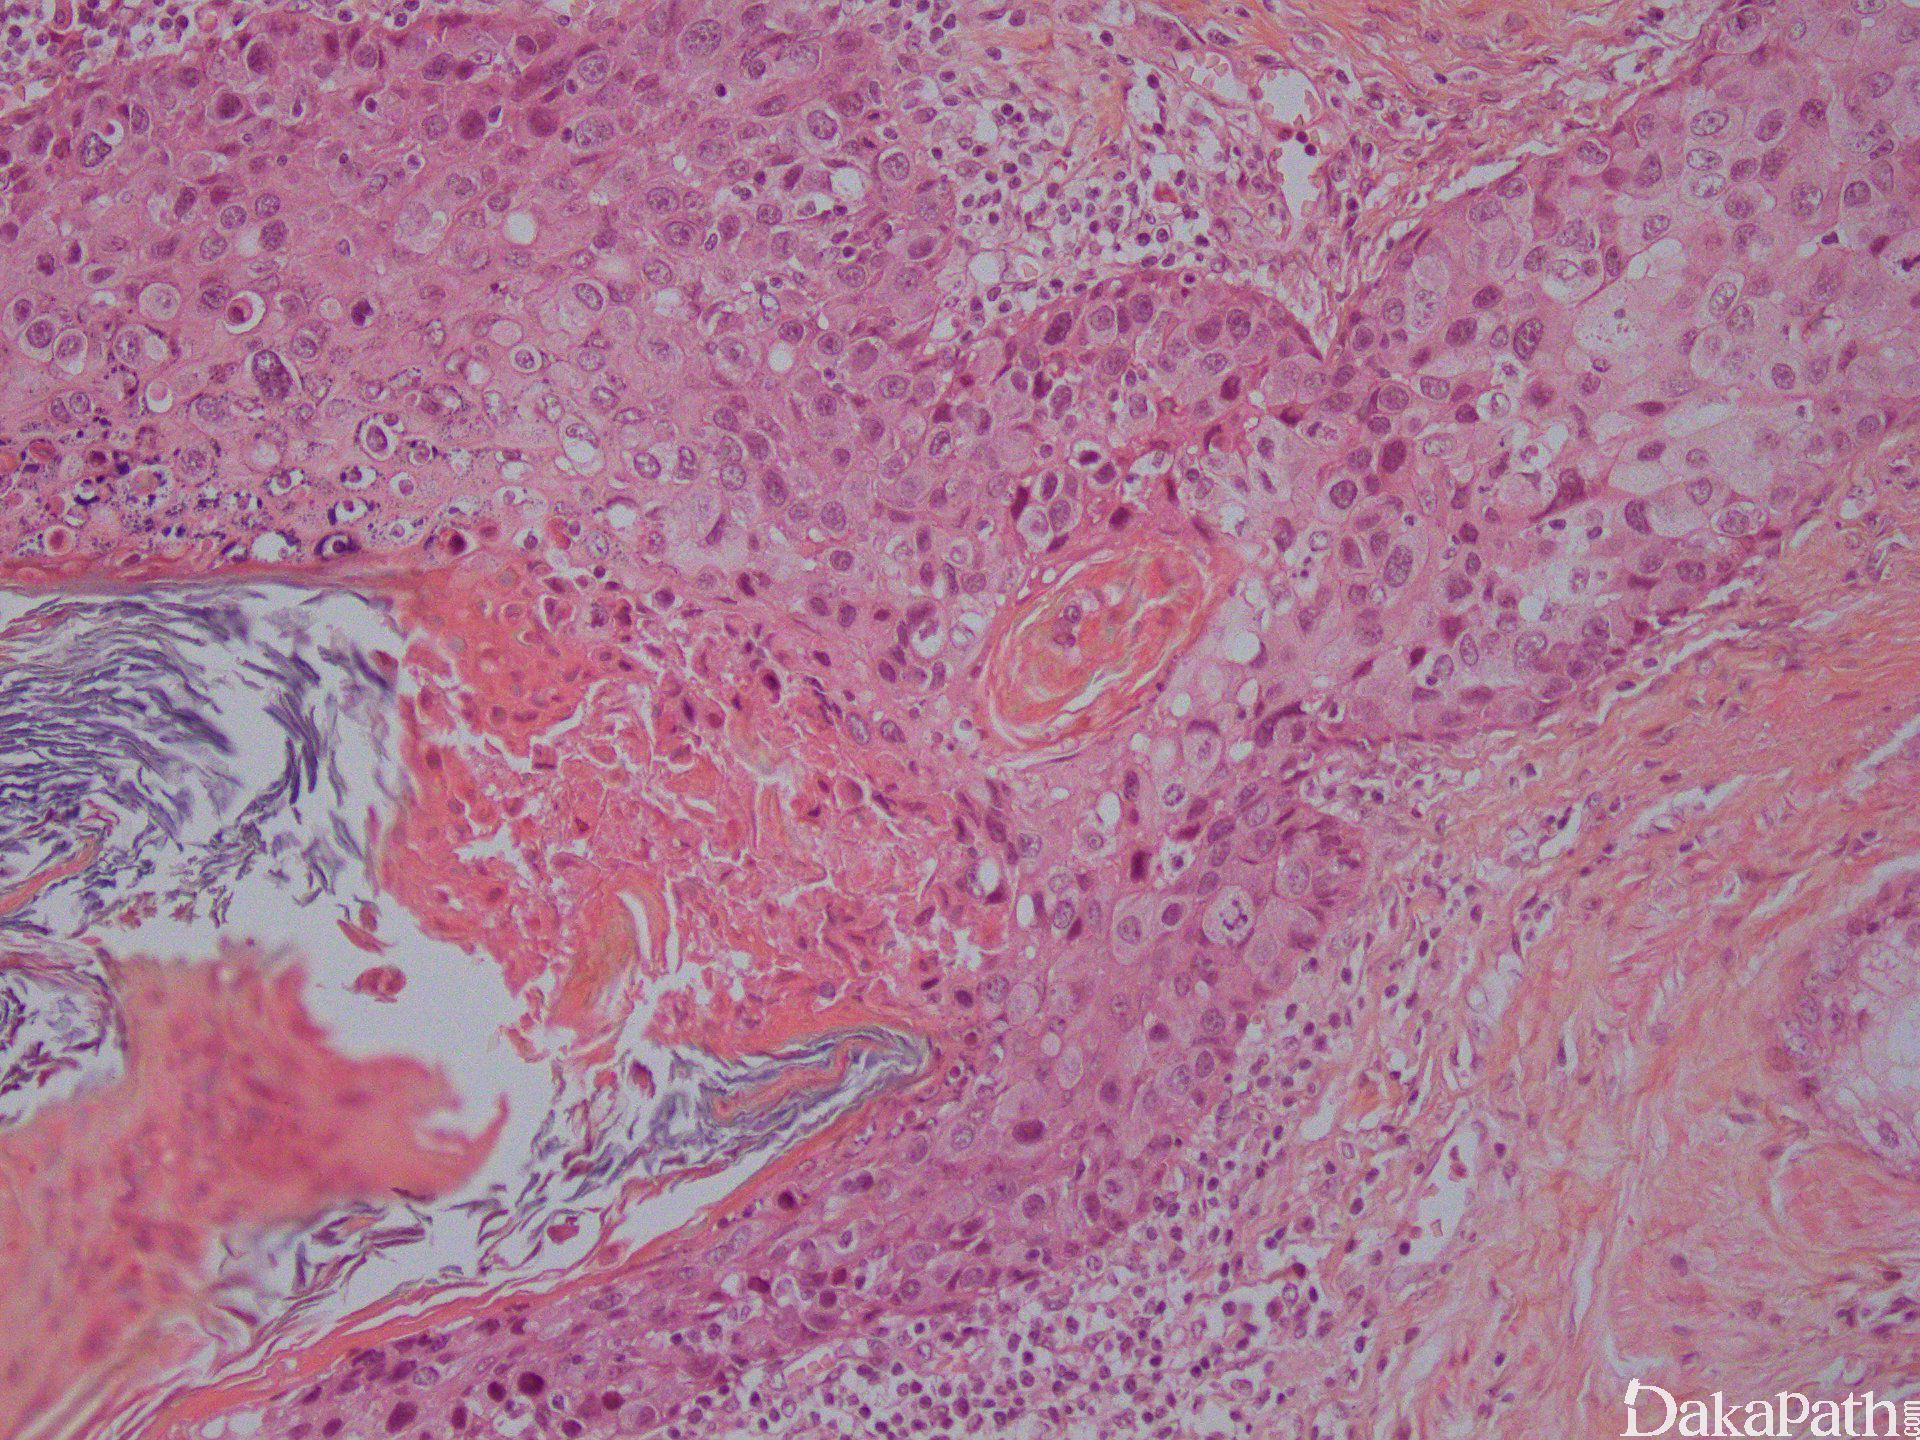

乳头皮肤表皮内可见大的异型细胞;

大细胞可单个散在或小灶分布于表皮内;

胞浆丰富,淡染、透明或嗜双色性,核大,核仁明显,与周围细胞明显不同;

表皮增生、角化亢进、角化不全常见;

真皮可见淋巴浆细胞浸润;